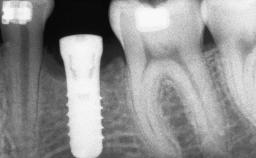

Ridge Preservation and Implant Placement for a Fixed Dental Prosthesis After a Car Accident

It is well known to clinicians that any removal of teeth will, over time, cause the dimensions of the alveolar ridge to be reduced by resorption of the bundle bone and by changes related to external modeling. This development is particularly evident in the crestal region with its thin buccal bone that consists of bundle bone almost entirely. The facial bone will rapidly resorb as blood supply from the periodontal ligament gets disrupted (Araújo and Lindhe 2005). There is no reason why traumatic tooth loss should not have the same consequences. It takes more than achieving implant osseointegration for a treatment outcome to be considered successful. No deficiency of bone or soft tissue is acceptable when an ideal esthetic outcome is the goal. Several articles (Sanz and coworkers 2011; Vignoletti and coworkers 2011) have reported on techniques of improving the alveolar ridge for implant treatment, notably focusing on protecting tissues from resorption.

# of Implants 4

Type of Implants One-Piece|Reduced-Diameter